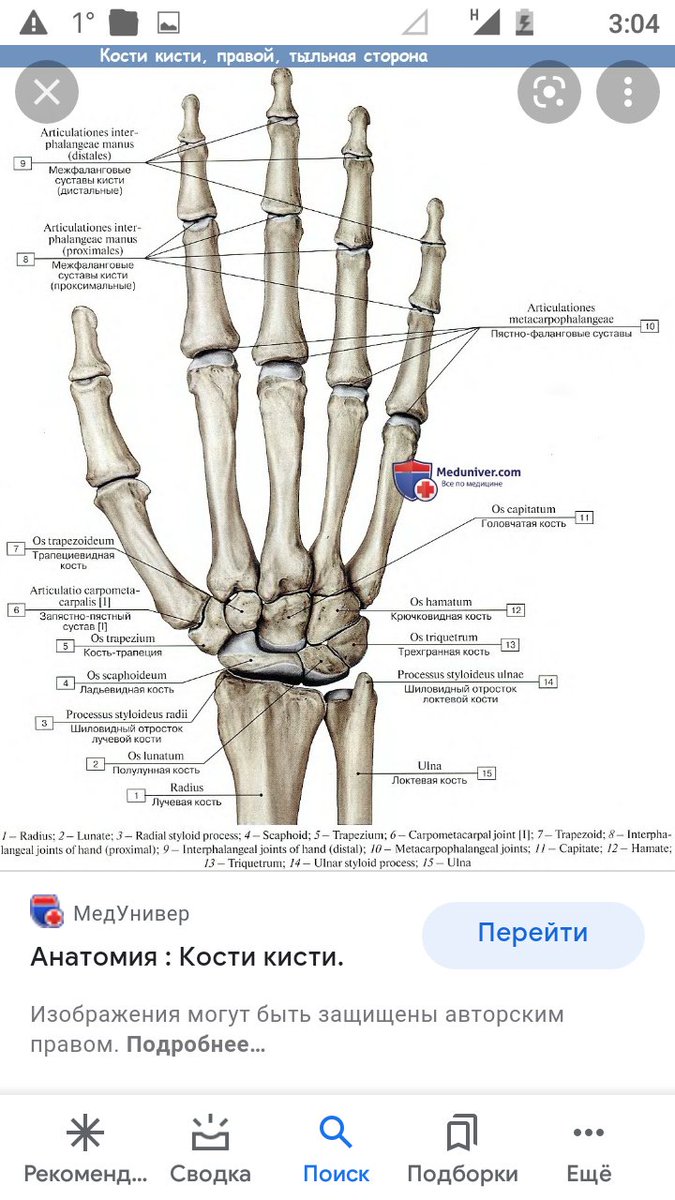

Анатомия кисти руки и строение костей